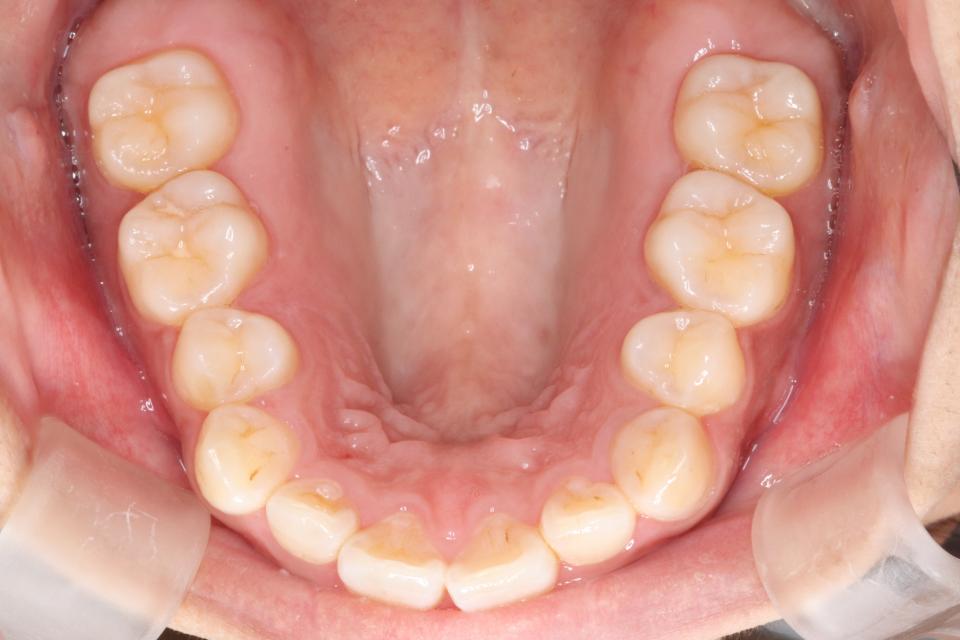

矯正治療前

30代女性の患者さんです。

前歯の歯並びが気になり来院されました。

マウスピース型の矯正治療装置を使用し、前歯の歯並びのみの改善を行いました。